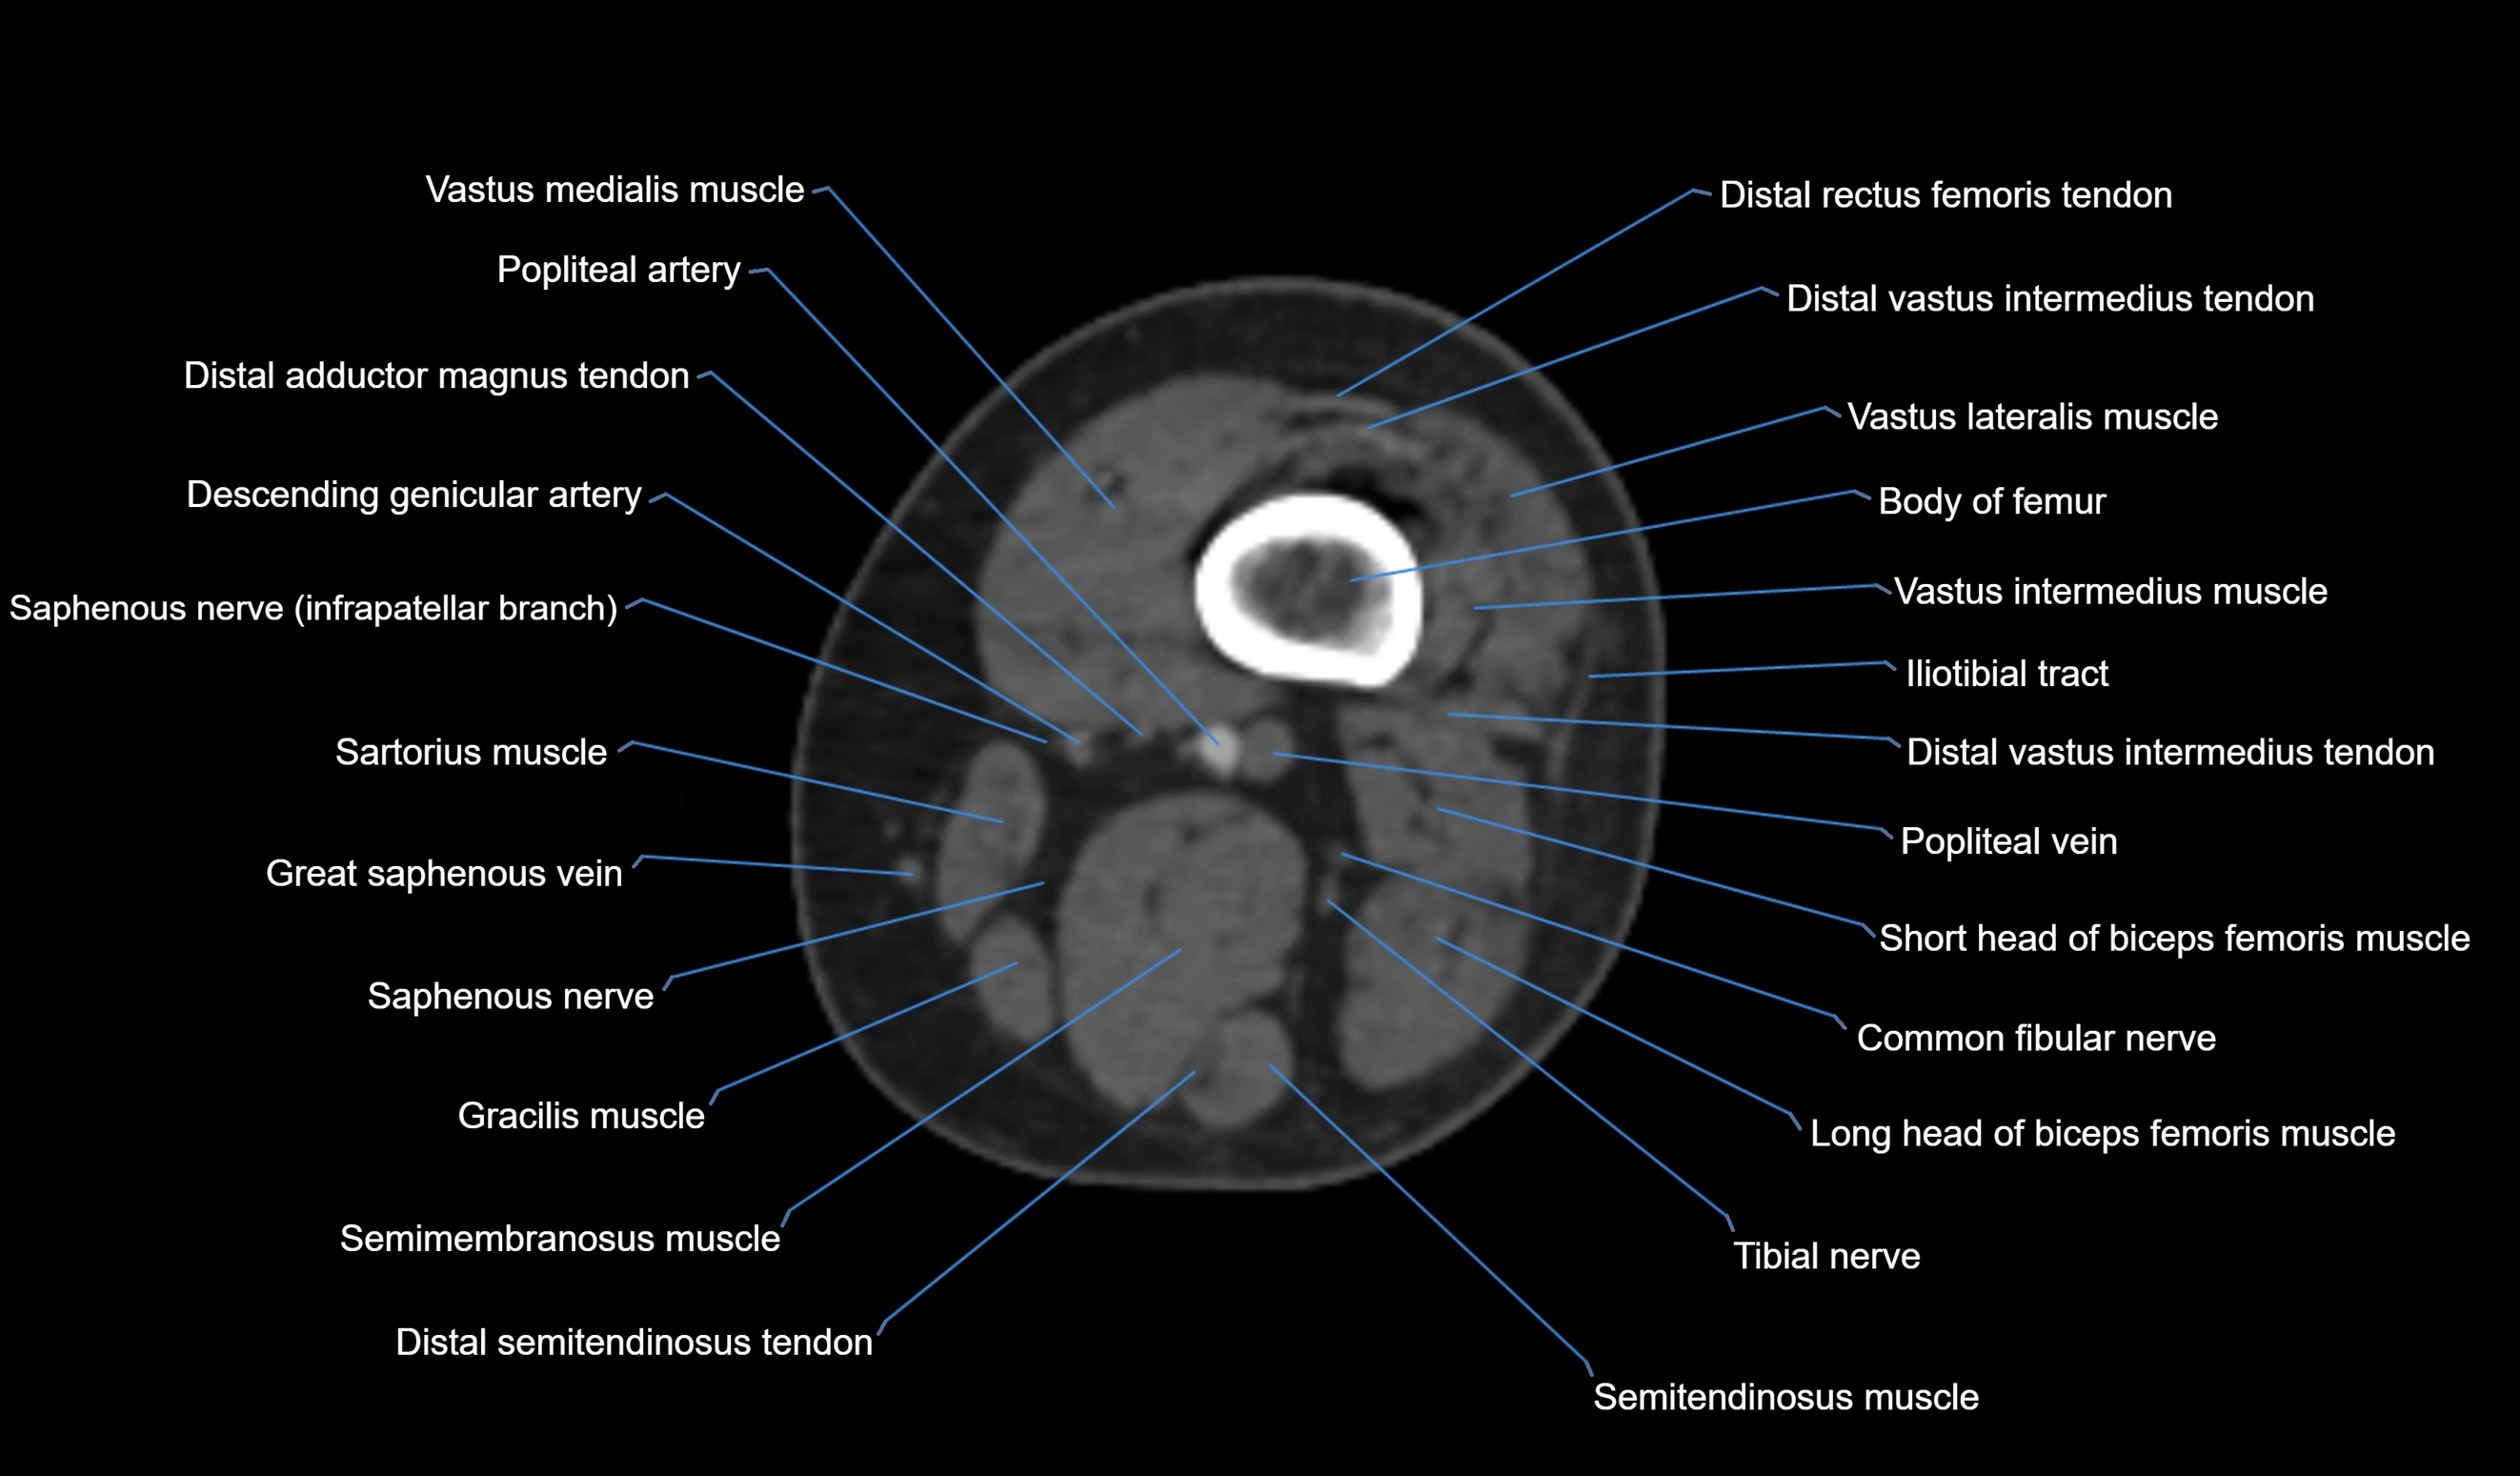

- Biceps femoris muscle (Short head)

- Body of femur

- Common fibular nerve

- Distal adductor magnus tendon

- Distal rectus femoris tendon

- Distal vastus intermedius tendon

- Distal vastus lateralis tendon

- Gracilis tendon (Distal)

- Popliteal artery

- Popliteal vein

- Sartorius muscle

- Semitendinosus muscle

- Tibial nerve

- Vastus lateralis muscle

- Vastus medialis muscle